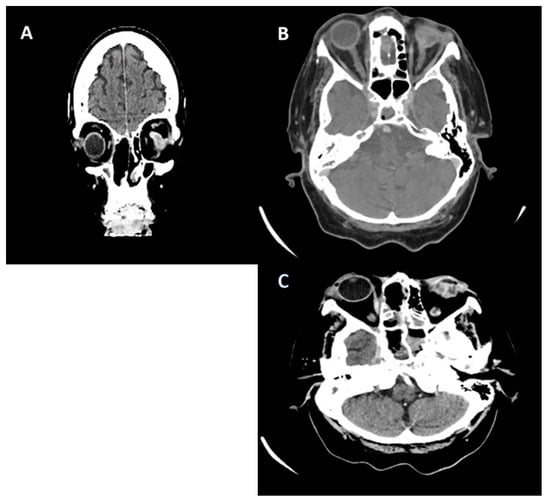

2.1. Case 1

2.2. Case 2

2.3. Case 3